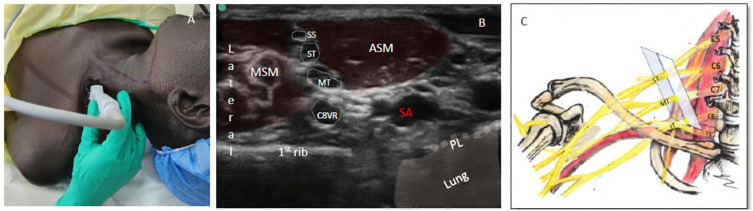

Methods: We developed a novel ultrasound-guided regional anesthesia technique-the Single-entry Selective Trunk Block (S-SeTB)-which targets the superior trunk (ST), middle trunk (MT), and C8 ventral ramus (C8VR) with local anesthetic diffusion to the inferior trunk (IT). The procedure uses one skin entry point to deliver three injections and is combined with a superficial cervical plexus (SCP) block using the same entry and ultrasound plane. Over 600 procedures were performed in field hospitals operated by the International Committee of the Red Cross, with observations documented.